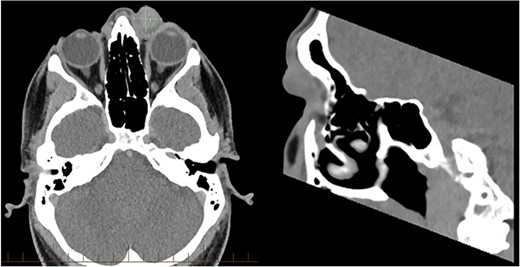

Computerised tomography (CT) and magnetic resonance imaging (MRI) were performed to further define the lesion as seen in Figs 1 and 2.

CT of the orbits demonstrated a 21 × 19 mm soft-tissue mass at the medial canthus with mass effect on the adjacent globe and no evidence of infiltration.